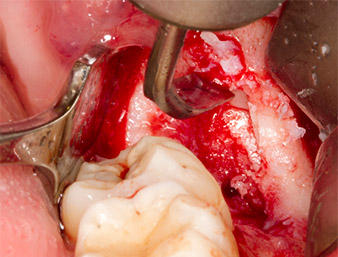

To expose the root remnant with as little trauma as possible to the tissue, a further instrument was used (Piezomed S2) that is primarily indicated for preparing the lateral window in augmentations of the sinus floor. The diamond-coated ball was additionally used to smooth sharp bone edges (Fig. 6 and 7). All the Piezomed attachments were used with the relevant automatic default setting without booster function.

Piezomed S2

Fig. 6: The root remnant is carefully exposed with a diamond-coated spherical instrument (Piezomed S2), bone edges are smoothed.